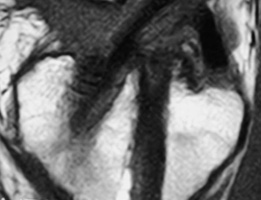

La cirugía de revisión del LCA actualmente es una técnica frecuente recibiendo habitualmente en nuestra práctica pacientes que han fracasado no sólo con la cirugía primaria sino que también en algunos casos con fracasos en cirugías posteriores de revisión. (Fig. 6 A-B y C)

| Figura 6A: 3er revisión LCA(Nótese los túneles femorales anteriores y tibial posterior previos) | Figura 6B: Fijaciones con cross pin previas a nivel femoral | Figura 6C: Nótese el túnel tibial previo muy posterior |